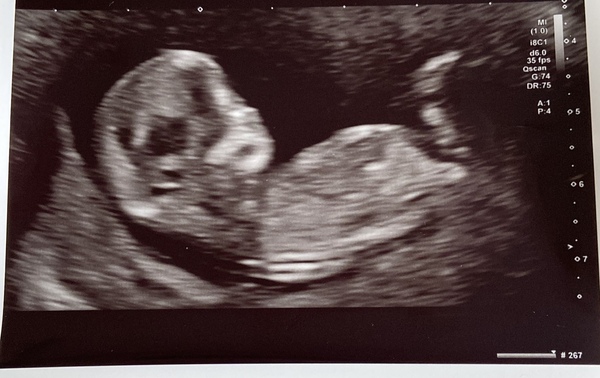

12 Week Ultrasound - Flat Back of Head?

We went for our 12-week scan this week. The first sonographer kept looking at our baby’s head and then went to get a second opinion from a second sonographer who agreed we should come back in two weeks to check how the flat part of the skull is progressing. Aside from this we were told everything else is as it should be and to quote the second sonographer “strong ventricles” were visible…